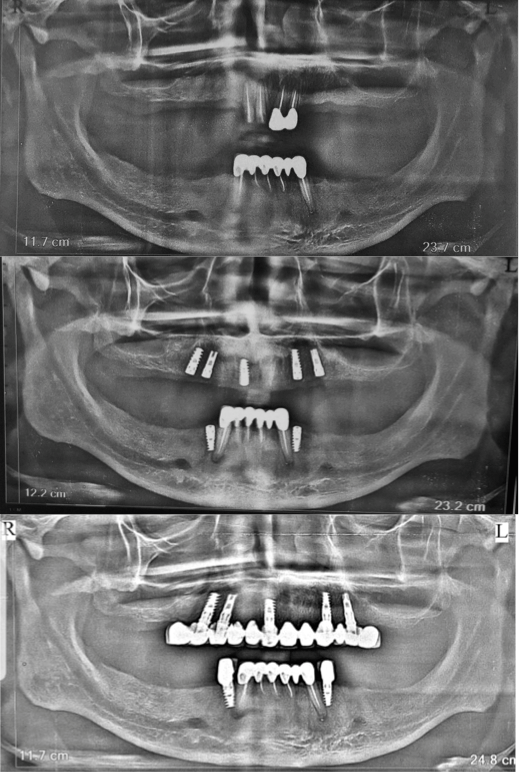

Full Mouth Rehabilitation

Card image